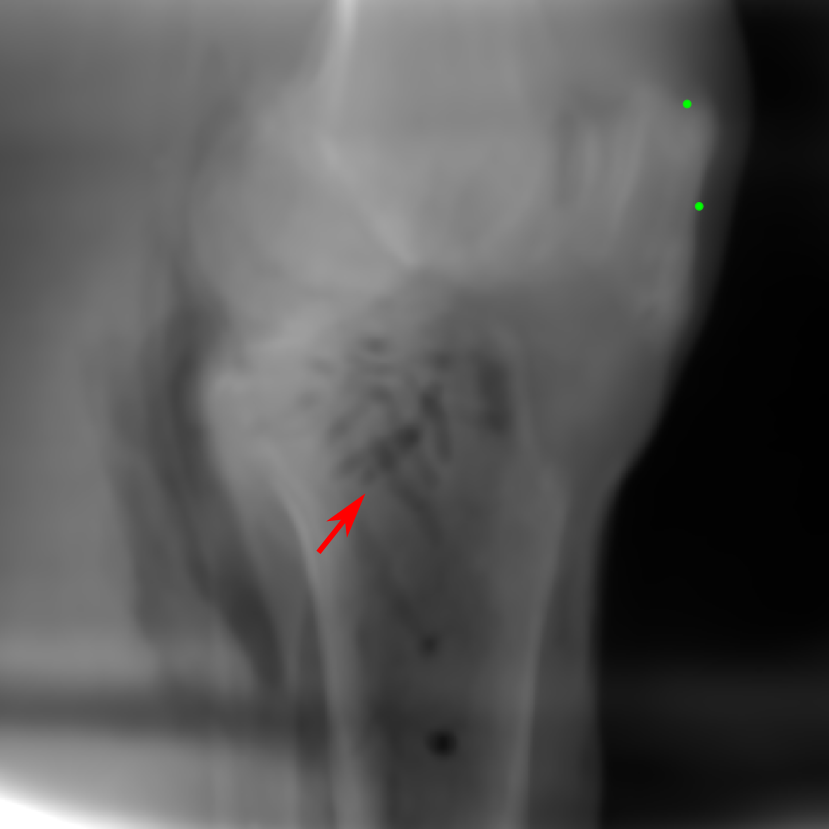

The results of one exemplary patient for cephalometric imaging are displayed in Fig. 11. In the 0superscript00^{\circ} perspective projection image (Fig. 11(b)), because of perspective deformation, anatomical structures from the left and right sides do not overlap well, especially for the mandible as indicated by the red arrow in Fig. 11(b). It causes inaccuracy in determining the cephalometric landmark of the gonion. The difference of Fig. 11(b) to the reference Fig. 11(a) is displayed in Fig. 11(c). A scale bar of 2 mm is displayed in Fig. 11(c), as 2 mm is the clinically acceptable precision for cephalometric landmark detection. It is obvious that many anatomical structures in the 0superscript00^{\circ} perspective projection images have position shifts larger than 2 mm. In the prediction image (Fig. 11(d)) using a single 0superscript00^{\circ} view in Cartesian coordinates, perspective deformation is reduced to some degree, as displayed in the difference image Fig. 11(g). For example, the mandible region has less error. However, Fig. 11(g) also indicates that many bony structures still have deviations larger than 2 mm. The results of learning from dual complementary views in Cartesian and polar coordinates are displayed in Fig. 11(e) and Fig. 11(f), respectively. Both images have little perspective deformation, as revealed by their difference images in Fig. 11(h) and Fig. 11(i). Nevertheless, in Fig. 11(e), two dark regions are indicated by the two arrows, which are better visualized in the difference image Fig. 11(h). The results of TransU-Net are displayed in Figs. 11(j)-(o). In Fig. 11(m), the structures near the porion landmark are distorted, for example, the ear canal indicated by the arrow. Consistent with Pix2pixGAN, perspective deformation is largely reduced in the both TransU-Net prediction images using dual complementary views in Cartesian and polar coordinates.

U-Net SSIM 0.8680 0.9257 0.9682 0.9719